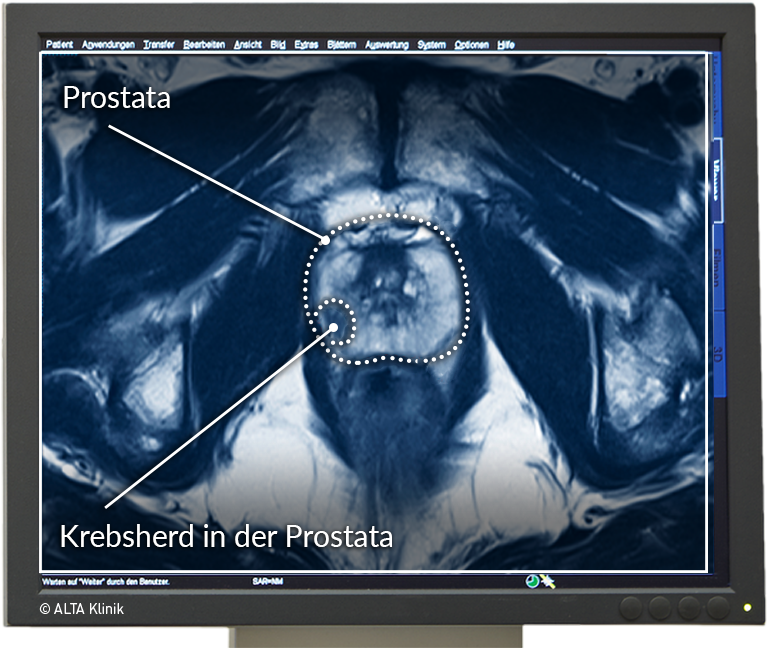

Sichere Prostatavorsorge mittels MRT-Untersuchung der Prostata Erstmals Geburt im MRT aufgenommen

Multiparametric MRI of the Prostate – ALTA Klinik MRT อิสรภาพ ลัดเลาะกินเที่ยวร้านเด็ดใกล้สถานีรถไฟฟ้าย่านฝั่งธน | Becquetwinery

Prostata MRT – die sichere und schmerzfreie Alternative zur Biopsie MRT อิสรภาพ ลัดเลาะกินเที่ยวร้านเด็ดใกล้สถานีรถไฟฟ้าย่านฝั่งธน | Becquetwinery